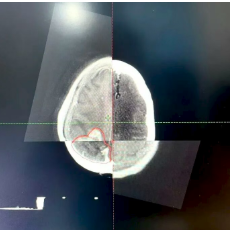

VitalBeam直线加速器落户达州市第三人民医院啦!现已正式投入使用。这个机器可大有来头,它就是在放疗界被誉为“放疗超人”的美国高端进口直线加速器,全市仅此一台。 三院肿瘤科开展放疗工作已有7年,年均放疗约6800人次,科室配套设施设备完善,放疗团队专业可靠,放疗技术成熟。VitalBeam直线加速器的引入使用,将填补我市精准放疗领域的空白,为三院放疗技术达到先进水平提供坚实保障,更为广大肿瘤患者带来新希望。 什么是放疗? 通俗来讲,放疗就是利用直线加速器产生的高能X射线,聚焦照射到肿瘤所在部位,从而杀灭肿瘤细胞。 据世界卫生组织(WHO)统计,目前约70%的恶性肿瘤病人需要在不同时期接受放疗。肿瘤患者中有45%是可以治愈的,其中放疗占18%,手术治疗占22%,化疗等其他治疗方式占5%。 VitalBeam直线加速器的四大优势 1、更快速 剂量率较以往的600MU/min大幅提升,最大可达到1400MU/min,对应的治疗时间从以往的15分钟以上缩短至平均3分钟左右。同时,治疗系统还通过“智能”自动化操作,进一步加快了治疗速度,缩短了治疗时间。这不仅让一些之前无法进行治疗的患者有了治疗机会,还能减少因治疗时间过长而带来的系统性误差和风险。 2、更安全 一方面来自于它的准确性,另一方面它在治疗区域之外的剂量跌落非常快,从而能有效地保护正常的组织和器官,此外,它还具备智能化的自动提示功能,可避免一些不必要的操作。 3、更精准 精度为0.5mm,相比于以往的1mm,精度提高了一倍。其次,它有一整套影像系统,能进行图像引导下(IGRT)的精准治疗,即使肿瘤在治疗期间因患者的呼吸而不断移动,系统依然可以准确捕捉肿瘤的位置。 4、更多功能 功能全面,可开展体部立体定向放射治疗(SBRT)、放射外科治疗(SRS)、图像引导放射治疗(IGRT)、呼吸门控治疗等多种先进治疗技术。 实际案例 使用VitalBeam直线加速器对一例脑胶质瘤患者放疗的步骤 放疗靶区勾画 采用MR和CT图像融合的方式,可准确区分病灶边界。 放疗计划设计 使用非共面旋转容积调强先进技术(VMAT)。 计划评估 处方剂量完全覆盖靶区(红色区域),靶区外正常组织剂量迅速跌落(正常组织受量更低)。 放疗实施 放疗时使用加速器自带锥形束CT进行图像引导(IGRT),自动对准靶区中心,实现了放疗可视化,放疗更加精准。 严格质控,保障质量 三院配备了先进的质控设备:晨检仪、二位矩阵和三维验证系统,定期进行加速器质检和放疗计划验证,确保加速器精度和放疗质量。 VitalBeam直线加速器主要适用于以下疾病 ●头颈部肿瘤:鼻咽癌、口腔癌、口咽癌、颈部肿瘤等; ●胸部肿瘤:肺癌、食管癌、乳腺癌、淋巴瘤及胸腺瘤等; ●腹部肿瘤:贲门癌、胃癌、肝癌、胰腺癌、结直肠癌等; ●泌尿生殖系统肿瘤:宫颈癌、卵巢癌、肾癌、生殖细胞肿瘤等; ● 四肢软组织肿瘤及各部位骨转移瘤; ●部分良性病变:垂体瘤、甲状腺眼凸等。 VitalBeam直线加速器的到来,无疑为三院肿瘤治疗注入了强大动力,我们将以更先进的技术、更专业的团队,为患者提供更优质的医疗服务,守护每一位患者的健康。